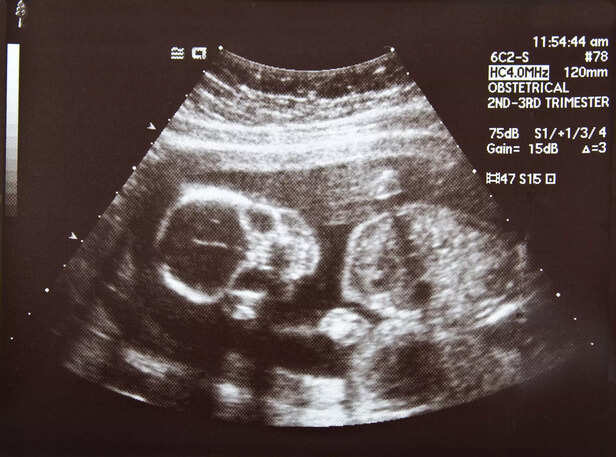

b. Fetal Surveillance Techniques

ultrasound

Additional fetal surveillance techniques, such as fetal ultrasound and scalp blood sampling, may be employed to evaluate fetal status and response to interventions. These assessments guide clinical management and help determine the optimal timing for delivery.